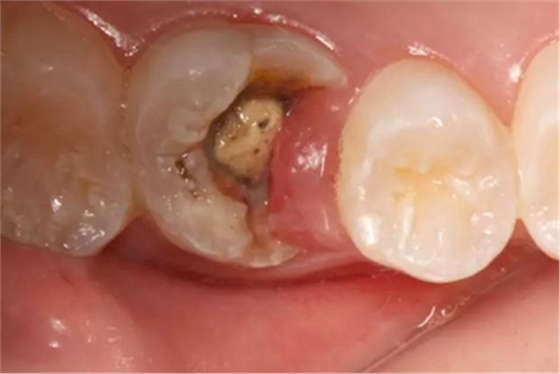

病例一 女性,20歲,大學(xué)生,要求補牙,檢查口內(nèi)可見A6大面積缺損,近中牙齦息肉,拍X片,根管充填物略差,但根周未見明顯陰影,口內(nèi)檢查無叩痛。建議患者冠延長手術(shù)+高嵌體修復(fù)。

患牙遠(yuǎn)中邊緣嵴完整,強度沒有降低,故擬保留遠(yuǎn)中邊緣嵴,高嵌體修復(fù)。首先去除腐質(zhì)及原墊底材料,流體樹脂+3M Z350XT樹脂墊底。局麻下行冠延長手術(shù)。在此需要提及個人的一個觀點。冠延長手術(shù)原則上要求3-6個月以上才能永久修復(fù)。但是個人喜歡后牙肩臺建立在齦上,所以修復(fù)后的修復(fù)體邊緣位于牙齦上方1mm,對牙周的愈合影響較小(如果為齦下邊緣則要慎重),故該患者術(shù)中按照齦上邊緣的設(shè)計進行冠延長手術(shù)。以下為術(shù)中: